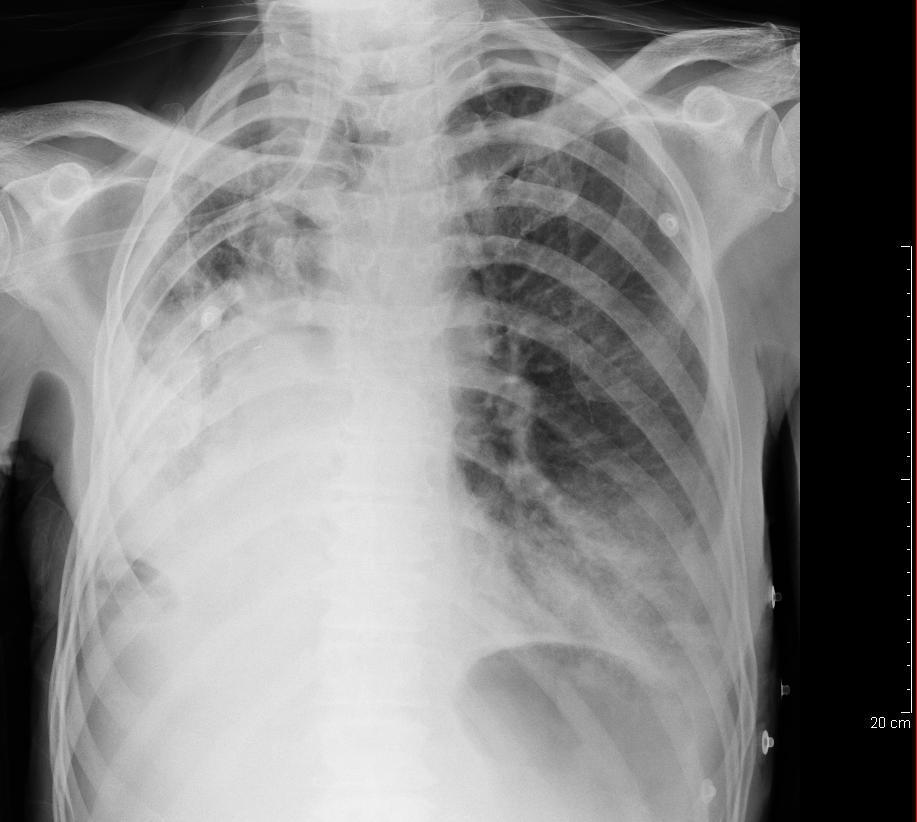

Rib Fractures Supine Haemothorax